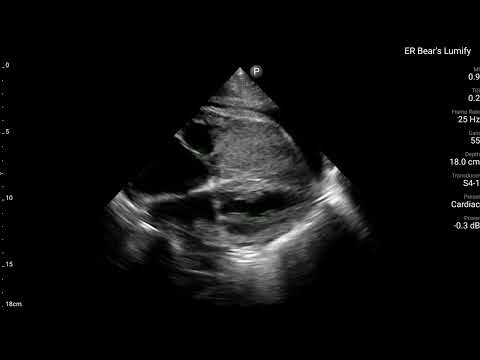

當時,在Bedside也有幫病患做echo。

可以清楚看到RV整團mass lesion,在PLAX打開color flow,在RV也沒有明顯flow。在PSAX view可清楚看到RV dilate with D-sign。A4C view更是清楚看到RV塞滿東西。不管是tumor還是thrombus,基本上已經造成RV strain(RV明顯dilate)。進而看到ECG上面的變化。